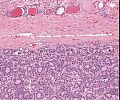

A63 Basaliom

Basaloide Tumorformationen mit palisadenartiger Begrenzung der Zellnester.

A63 Basaliom

Tumorinfiltration, ausgehend von der Epidermis

Basaliom_A63.png

Erkennbar sind Tumorzellnester mit pallisadenförmiger Anordnung der Tumorzellem am Rand